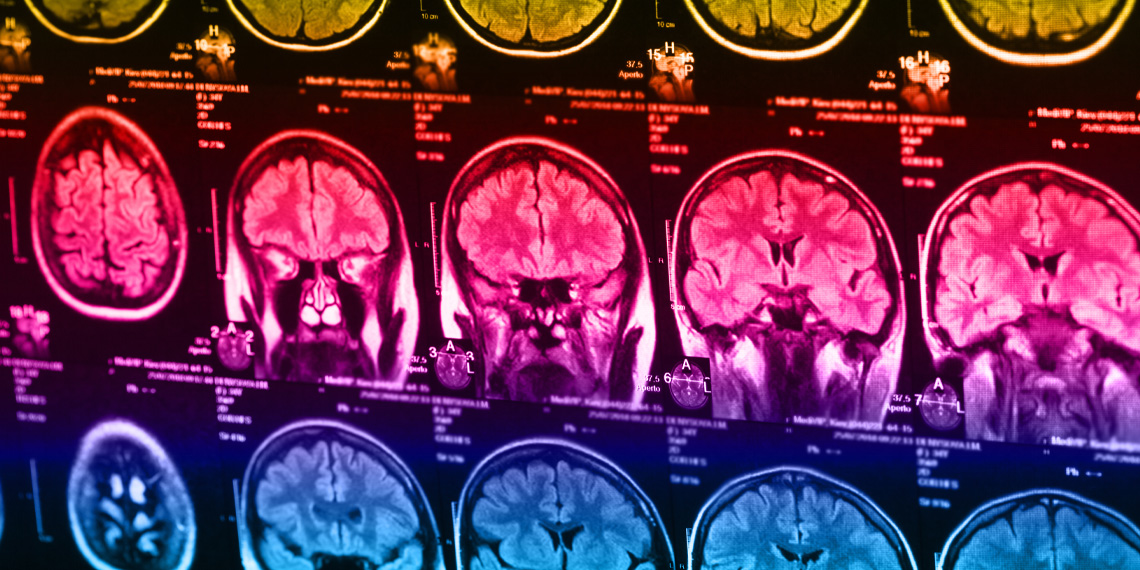

Дальше всех отправили в МРТ — смотреть на их мозги в момент высшей драмы. Тут в дело вступает старая добрая Cyberball — виртуальный пинание мячика. Им рассказывали, что играют якобы с реальными людьми. На самом деле — с искусственным интеллектом, чьи фотки убеждают, что где-то там кто-то и правда кидает мяч.

Сначала — радость: все играют вместе, мяч летит к нашему участнику регулярно. Потом — облом века: мяч внезапно забывает дорогу обратно, и «друзья» полностью игнорируют героя эксперимента. Мозг тех, кто жить не может без смартфона, тут же выстреливает тревожность в зону средней поясной извилины (это такой мозговой пост караула за болезненными чувствами). Контрольная группа же реагировала как взрослые: активизировались области, отвечающие скорее за внимание, чем за эмоциональные муки.